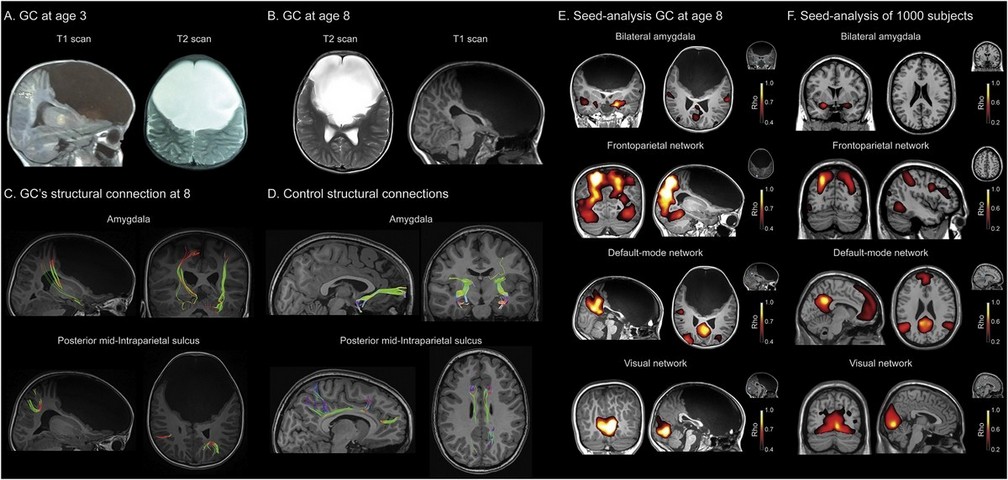

"El caso de Gabriela es absolutamente excepcional, no tiene registro en la medicina. Hace dos años nos enteramos de su padecimento y empezamos a investigar a distancia y en viajes que realizamos un grupo de médicos argentinos a Cali", explicó a Infobae el doctor Agustín Ibáñez, director del Instituto de Neurociencia Cognitiva y Traslacional (Incyt), de triple dependencia: Ineco-Favaloro-Conicet.

"Gabriela carece del lóbulo frontal, que es la parte más evolucionada que tiene el cerebro. Allí se determina el control de la conducta, el procesamiento de las emociones, los deseos, las llamadas ejecutivas de determinada acción, el lenguaje y otras más. Esa porción cerebral es realmente como una computadora compleja, donde se mantienen más conexiones. La niña presenta solamente un 10% de esa corteza prefrontal, pero al estudiarla vimos que no tiene ninguna conexión cerebral", sostuvo Ibañez.

Antes de viajar a conocerla, el doctor Ibañez vio las resonancias efectuadas en su cerebro y pensó que no caminaba, por carecer de corteza motora, o que no hablaba, porque le faltaba las áreas de Broca.

Sabíamos por los profesionales contactados allá en Colombia y por los estudios realizados que ella no tenía los lóbulos del cerebro cruciales para ordenar la conducta de una acción. Pero al conocerla , pudimos notar que podía comprender el lenguaje, realizar juegos simbólicos, tener conciencia y hasta resolver problemas complejos. Nos sorprendió enormemente", describió el profesional.

"Si bien las imágenes estructurales muestran la ausencia del lóbulo cerebral, la tractografía y conexiones de neuronas se reorganizaron de forma plástica desde su concepción en el seno materno y durante su niñez. También observamos que las conexiones funcionales, las redes por donde se transmiten las órdenes cerebrales se reorganizaron", aclaró el profesional.

"Eso significa que en condiciones de neurodesarrollo, el cerebro puede generar una plasticidad enorme al punto de desarrollarse casi normalmente. Fue una neuroadaptación del desarrollo cerebral increíble", precisó Ibañez.